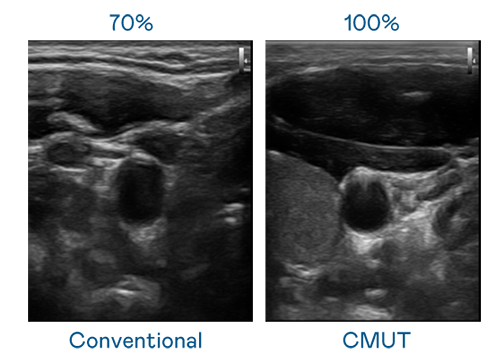

CMUT 技术是一种用电容式微机电元件来产生超音波讯号的技术。与传统 PZT 压电式技术相比,CMUT 频宽增加 30%,更宽频的超音波讯号让影像解析度大幅提升,是实现高影像品质医疗超音波扫描、促进精准医疗发展的关键技术。

大频宽带来超清晰影像

超音波影像的解析度高低,首先取决于探头能发出的讯号频宽。伟德国际 CMUT 可提供高清晰的超音波讯号,提供高频宽、高灵敏度、影像纹理细节更高的超音波影像,协助医护人员缩短影像判读时间及利用精准的医疗影像进行诊断。